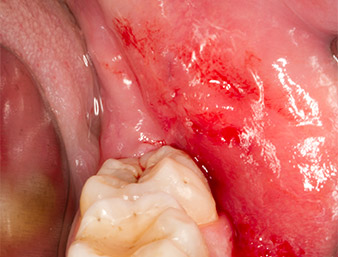

La plaie cicatrise sans complications (Fig. 17) et les fils sont enlevés au bout de sept jours. Le patient retrouve une sensibilité normale. Les douleurs ont cessé.

Situation après le retrait des fils

Fig. 17 : Situation après le retrait des fils 7 jours après l’extraction : la cicatrisation